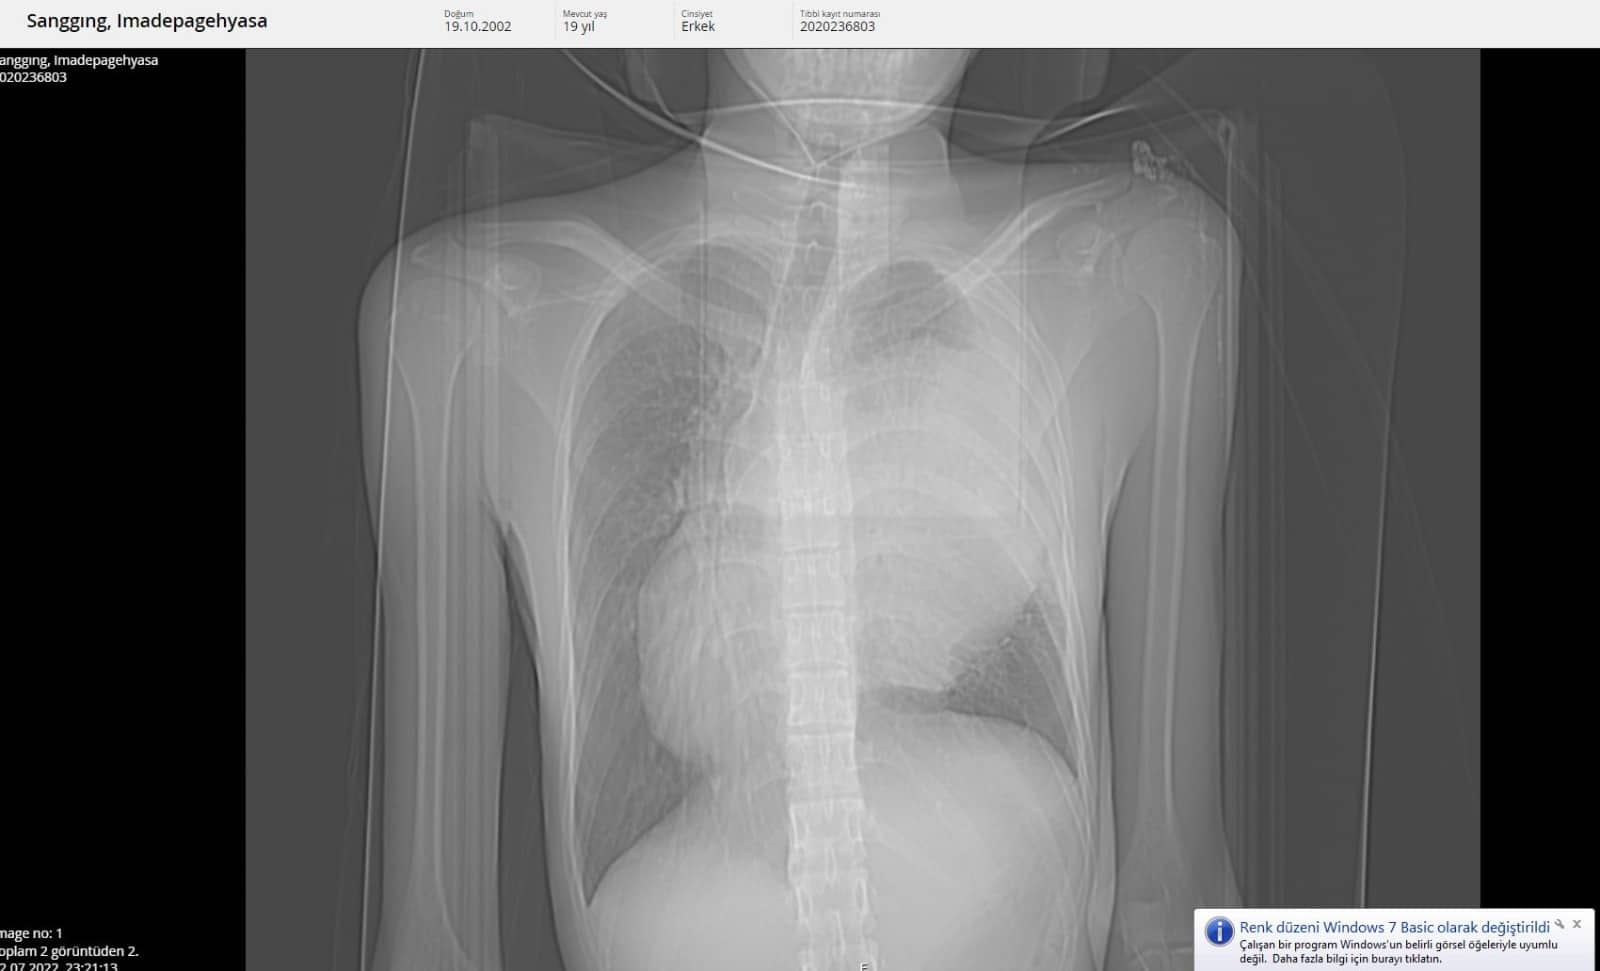

Tatil için Alanya’ya gelen 19 yaşındaki Endonozyalı I Made Pagehyasa Sanggıng, ağzından öksürükle birlikte kan gelmesi şikâyetleri ile Alanya Eğitim ve Araştırma Hastanesi Acil Servise başvurdu. Yapılan tetkik ve görüntülemeler neticesinde Sanggıng’ın sağ akciğerin tamamen fonksiyon dışı kalmasına yol açan bir kitle tespit edildi.

Kitlenin ayrıca kalbe ve diğer hayati organlara da ciddi bir baskı oluşturduğu belirlendi. 19 yaşındaki hasta ALKÜ Tıp Fakültesi Göğüs Cerrahisi Anabilim Dalı Başkanı Dr. Öğretim Üyesi Oktay Aslaner tarafından acil ameliyata alındı. Başarılı geçen operasyon sonunda hasta yeniden sağlığına kavuştu. Eski sağlığına kavuşan I Made Pagehyasa Sanggıng’ın ilk ziyaretçisi doktoru oldu.

Dr. Aslaner operasyon hakkında bilgi vererek şunları söyledi: “Acile başvuran Endonezyalı hastamızda tetkikleri sonucunda sağ göğüs kafesinin içinde dev bir kitle tespit edildi. Kalbi tamamen karşı tarafa itmiş, sol akciğerin ana atar damarını nerdeyse kapatmış şekildeydi. Ekibimle birlikte ameliyata aldık. Ameliyatta sağ göğüs kafesinden iki akciğer arasında köken alan ve sol hemotoraksı dolduran 3 kilo ağırlığında bir kitle çıkardık. Sonrasında hastanın akciğeri açıldı, kalbi rahatladı, akciğer atar damarı normal hale geldi. Kitlenin tamamen çıkarılmasıyla birlikte hasta yeniden sağlığına kavuştu. İlerleyen tıbbi cihazlar ve hastanemizdeki yoğun bakım olanakları bu tür ilerlemiş tümörlere müdahale imkânı sağlamaktadır” dedi.